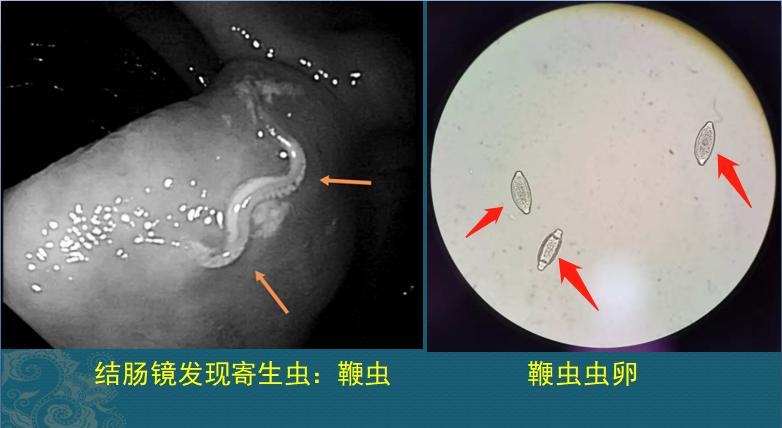

结果结肠镜让医生吓了一跳:

她的大肠表面盘着很多小虫子,这些虫子将虫体一端插入肠粘膜内掠夺营养,造成贫血和腹泻、体重下降。

这种虫子叫鞭虫,是一种土源性寄生虫,感染人类可引起腹疼、腹泻和贫血(乏力的原因)等。

鞭虫卵呈橄榄状,随粪便排出体外,在温暖潮湿、阴暗的土壤中大约3周发育为感染期,感染性虫卵内含有感染幼虫。

人类吃进沾染的感染性虫卵后,经消化液的作用,会在小肠内孵出幼虫,幼虫钻入小肠和结肠隐窝内发育长大,最后蠕动到盲肠和升结肠为主的大肠黏膜,发现这里温暖湿润,还有丰富的黏膜下营养,除了臭一点,非常适合鞭虫居住,于是它们就不再流浪,在这里安家落户逐渐发育为成虫(图1箭头),反正它们自己没有嗅觉,觉得粪块也不是那么难闻……

上面这个生长过程,大约需要2个月就能完成,也就是说,吃了被虫卵污染的生鲜蔬菜(尤其是根部土壤,容易沾染虫卵),只要60天左右就能在大肠内发现虫子。大多数病人没有症状,有些可以出现食欲减退、腹疼、腹泻、贫血等症状。